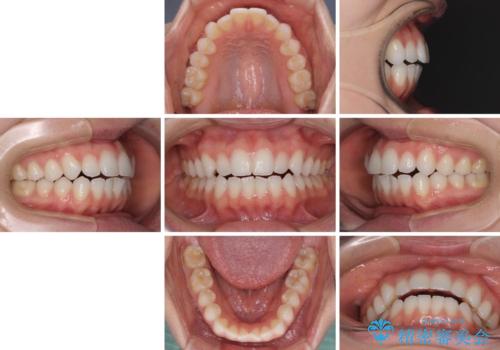

上下前歯が接触しない オープンバイトをインビザラインで改善

- 前歯の上下スペースによる食べにくさを気にして来院された患者様です。

インビザラインにより上下の前歯の隙間を閉じていくこととしました。

上下の奥歯を圧下させるようにすることで、前歯を接触させるように計画しました。

上下の隙間に舌が入り込むことがオープンバイトの原因であったため、舌の筋肉のトレーニングも並行して行い、後戻りの抑制を図りました。